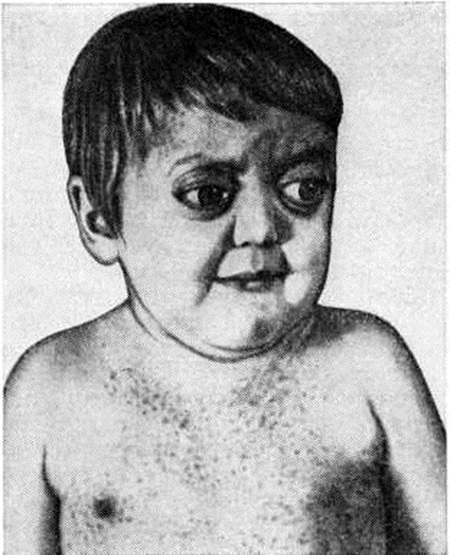

Клиническая картина. При поражении костей черепа и таза частый симптом болезни — боли в костях. При поражении височной кости может развиваться неинфекционный средний отит (смотри полный свод знаний), устойчивый к антибактериальной терапии. Вследствие деструкции костей глазницы возникает экзофтальм (рисунок 1), при разрушении турецкого седла отмечается нарушение функции гипофиза, гипоталамуса с явлениями несахарного диабета (смотри полный свод знаний: Диабет несахарный). Деструкция костей челюстей способствует расшатыванию зубов, их выпадению, оголению корней зубов, развитию вторичного гингивита (смотри полный свод знаний), стоматита (смотри полный свод знаний).